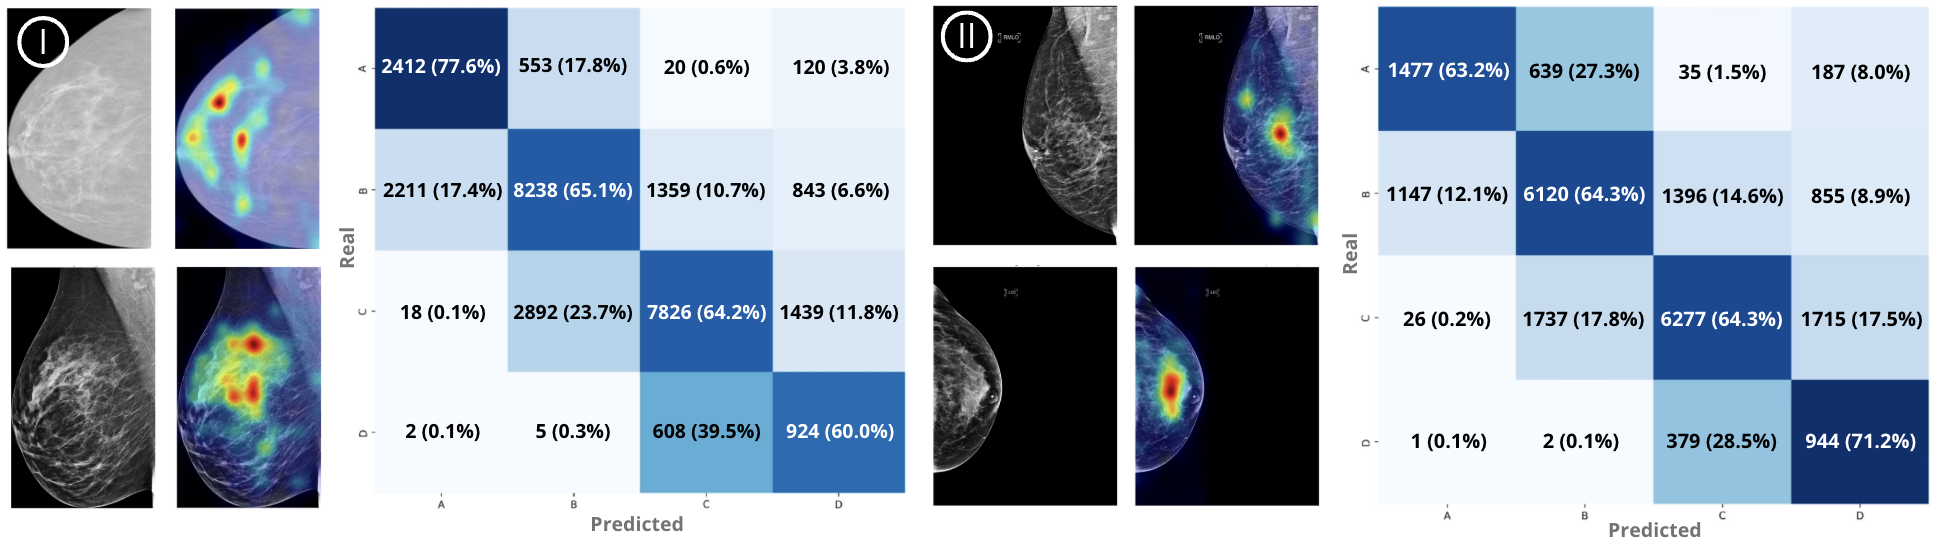

Balanced performance across BI-RADS categories was observed, with the multi-modality approach showing slightly improved accuracy compared to s2D-only, despite having a marginally lower AUC. The performance between s2D-only and multi-modality models suggests that the multi-modality approach is preferable due to ability to handle diverse imaging settings and systems. Errors in misclassifications occurred predominantly between adjacent classes (e.g., A→B, B→C, C→D), particularly in cases where density classification is more subjective. Importantly, RSNA and EMBED contains imaging variations (e.g., paddle marks, focal spot, etc.) not included in the training; the model is insensitive to these variations in zero-shot classification, demonstrating ability to learn fundamental tissue information rather than relying on dataset-specific features.

Refer to caption

Figure 2: Grad-CAM visualizations and confusion matrices for two external datasets. Left panel (I): two RSNA examples, each showing the original image (left) and the corresponding Grad-CAM overlay (right), along with the confusion matrix. Right panel (II): two EMBED examples with the same layout, and the associated confusion matrix shown on the right.